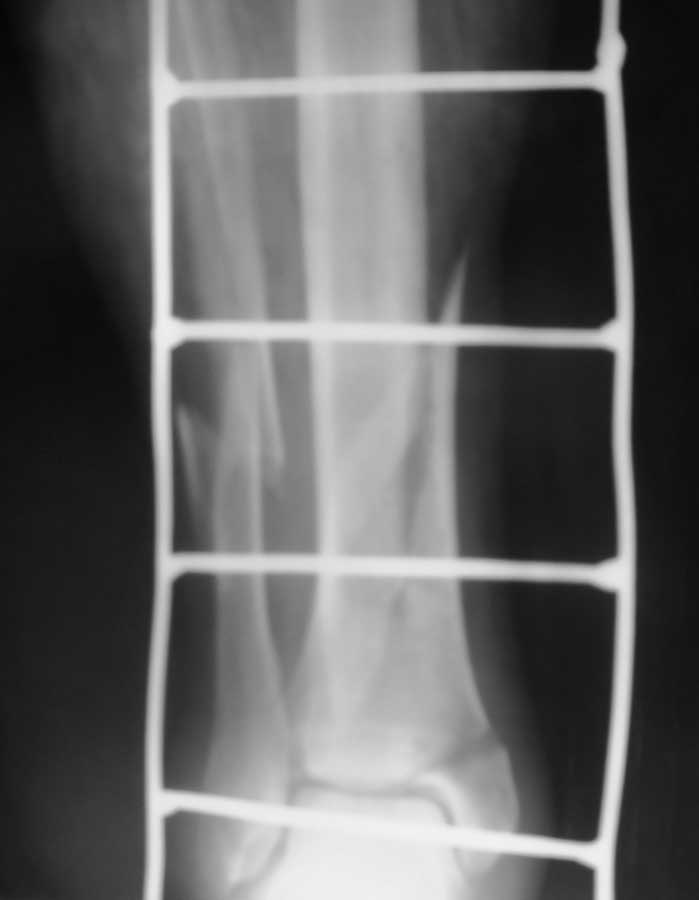

рентгенограмы

Уважаемый Дмитрий, не совсем понятно, когда Вы спрашиваете "что делать". Что делать с переломом или кожными дефектами, или и с тем и другим? Судя по фотографии дефект кожи в нижней трети обусловлен неврозом кортикала б/берцовой кости. Можно было бы попробовать сделать вторичную хирургическую обработку и перфорацию кости спицами дабы дать возможность снизу вырасти грануляциям, а на них уже выполнить аутодермопластику, либо попробовать закрыть дефект местно выкроив кровоснабжаемый лоскут, либо брюшко мышцы. Что касается АВФ, создается впечатление, что он недостаточно стабилен, а отломки немного перерастянуты, хотя по оси смотрится очень прилично. Желаю удачи.

Если судить по рентгенологической картине, то по всей вероятности имеем дело с механизмом непрямой травмы. Такие переломы при хорошем сопоставлении отломков срастаются в пределах 60-70 дней. На фото видны инфицированные раны, будто это участки некроза. Как бы там ни было созерцаемый на фото аппарат "неживой" и нефункциональный, будто его давно не касалась рука врача. Он полностью исчерпал себя, думаю, что он нестабилен. Предлагаю его демонтировать, дать конечности отдохнуть 2-3 недели, за это время провести курс комплексой терапии, как общей, так и местной, затем пациента вновь взять в операционную. Судя по фото, конечность атрофичная, поэтому есть возможность использовать кольца аппарата Илизарова малого диаметра, они фиксируют жестче. На дистальный фрагмент, судя по рентгенограммам, можно установить только одну опору. Чтобы она фиксировала хорошо, необходимо провести спицы (все с напайками с разных сторон) с хорошим перекрестом и разбросом. Для большей стабильности можно временно, на 3 недели, зафиксировать стопу 3/4 кольца и 2 спицами через пятку. На проксимальный фрагмент необходимо установить две опоры, причем нижняя из них должна быть расположена выше ран, чтобы легче было за последними ухаживать. Также провести по две перекрещивающиеся спицы с хорошим перекрестом и натяжением. Осколок можно дополнительно фиксировать спицей с напайкой за пределами ран ИЛИ В КРАЙНЕМ СЛУЧАЕ КОНСОЛЬЮ С НАПАЙКОЙ. Постарайтесь добиться максимально точной репозиции. Только так можно стабилизировать перелом, что позволит пациенту адекватно нагружать конечность, а это и есть путь к решению проблемы.

Кстати, репозиция у Вас неплохая, только большой диастаз между отломками. Если отломки еще податливы, то попробуйте его устранить.

С этим можно определиться только на операционном столе, исходя из податливости при устранении деформации. Судя по выложенным снимкам там сращения нет. Кстати, имеется наружная ротация дистального отломка большеберцовой кости порядка 15 градусов. Об этом свидетельствует то, что он на прямой проекции шире, чем проксимальный.